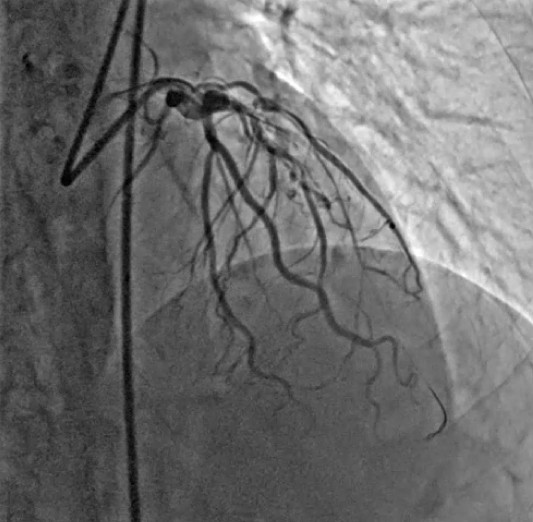

Chronic total occlusion of the mid LAD, with a blunt proximal cap. ¡¤ TIMI 0 flow distal to the occlusion. ¡¤ Distal LADvisualized via retrograde collateralfilling. ¡¤ Lesion length estimated to be >20 mm withmoderate calcification and tortuosity

Angiographyconfirmed a suitable anatomy for retrograde CTO PCI via septal-to-septalcollateral pathway using a single-catheter technique.Thepresence of navigable CC1–CC2 septal collaterals, clear visualization ofthe distal LAD,